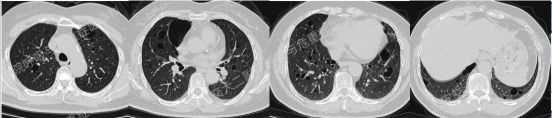

第一期埋下的伏笔,以下2例不同患者的胸部影像改变,又分别考虑什么疾病呢?答案呼之欲出,相信大家也越来越清晰了!